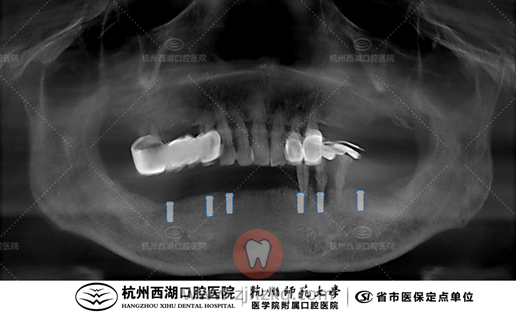

种植团队采用All-on-6即刻修复技术,为宋叔叔植入6颗种植体,即日戴牙完成半口修复。

术后CBCT照如下